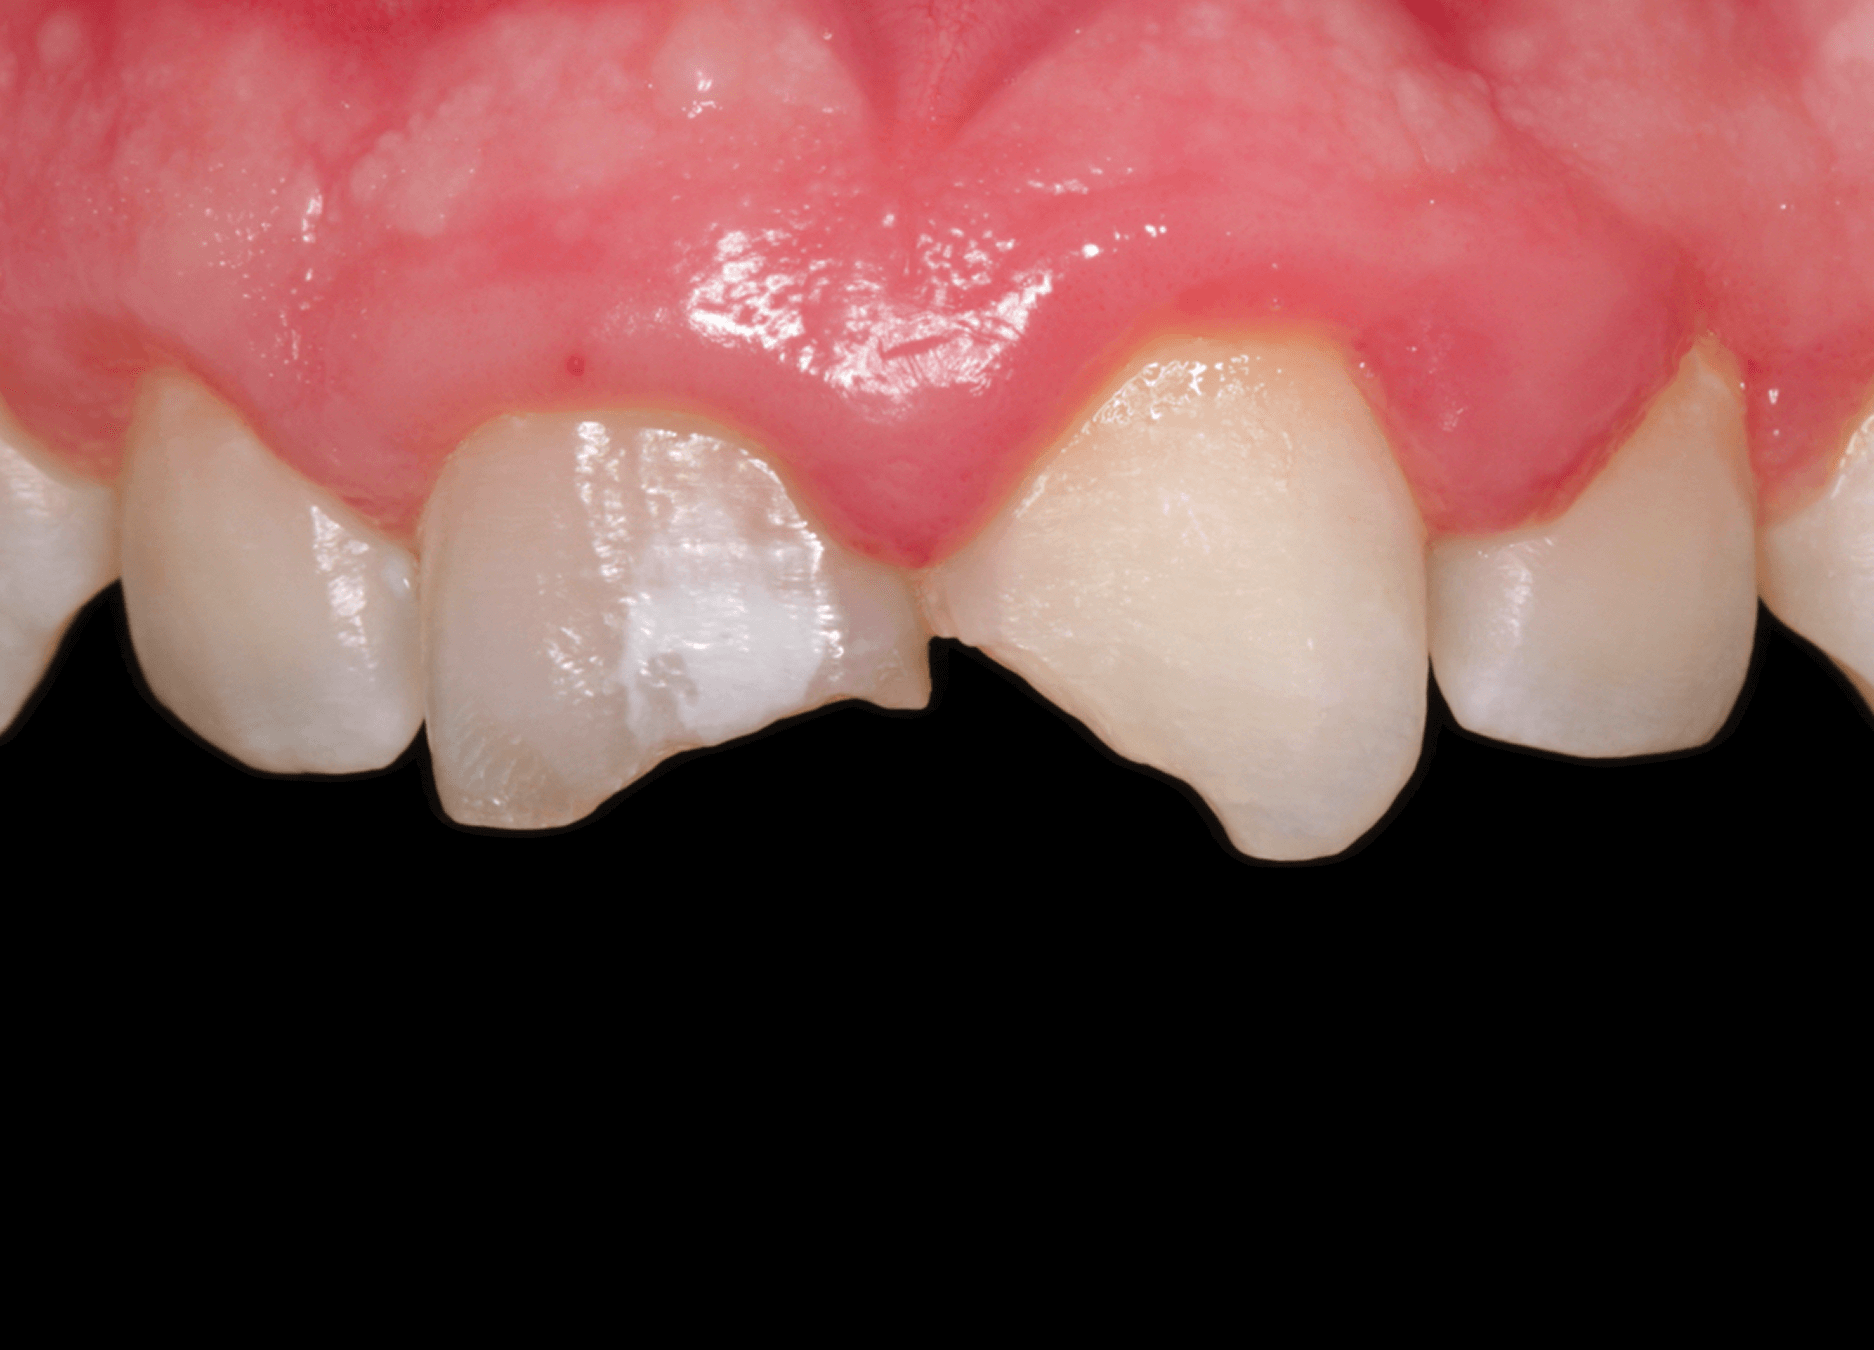

5. A control examination after 7 months confirmed successful bone regeneration in the periapical area of the treated tooth. Radiographic assessment demonstrated complete healing of the previous apical lesion with restored trabecular bone pattern.

Tooth #12 maintained normal pulp vitality, responding positively to cold and EPT sensibility tests. (Image 11,12,13)